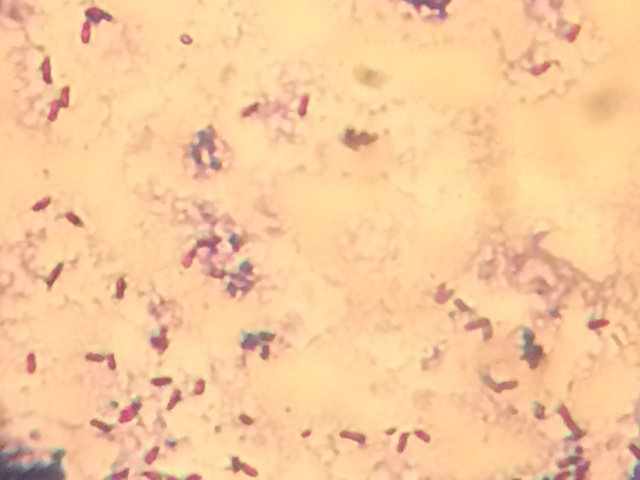

Çó´óÉñ¼ø¶¨ÊDz»ÊÇͬһÖÖ¾ú ·¢×ÔСľ³æIOS¿Í»§¶Ë |

¶¼Óÿ×ȸʯÂÌȾɫÊÔÊÔ£¬ÓÐÑ¿æß¾µ¼ìһϾÍÖªµÀÁË¡£ ·¢×ÔСľ³æAndroid¿Í»§¶Ë |

¶àÅàÑøÒ»¶Îʱ¼ä£¬Èç¹ûÓÐÑ¿æß½á¾§×ÏȾɫÊÇ¿ÉÒÔ¿´³öÀ´µÄ£¬ÈéËá¾ú²»²úÑ¿æß ·¢×ÔСľ³æAndroid¿Í»§¶Ë |